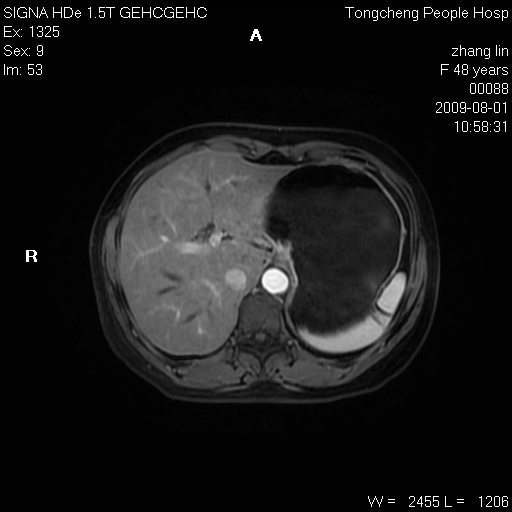

女,48岁。健康体检,彩超发现右肾占位性病变。平素健康。

临床诊断:右肾占位性病变,性质待定(囊肿?肿瘤?)。

上中腹部mr平扫+增强扫描,图像如下:

右肾上极见一类圆形病灶,t1wi呈等信号t2wi呈等高混杂信号,三期增强无强化,边界清---考虑囊肿出血。

同反相位均表现为等信号,病变无强化,考虑含蛋白的囊肿可能,弥散加权相或许有些帮助,

慢性胆囊炎